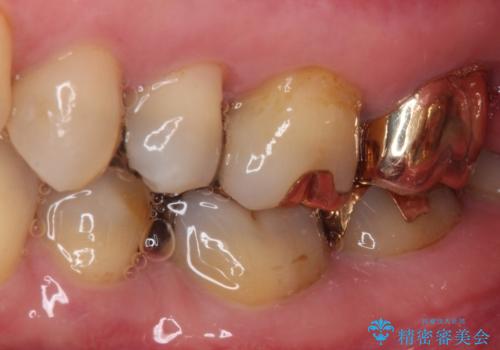

- 奥歯のクラウンが外れてしまったとのことで来院された患者様です。

土台の歯は、咬み合う下顎の歯と距離が近く、外れてしまったクラウンは、おそらく穴が空いてしまったのではないかと思われました。

距離が近いこと以外、特に大きな問題は認められなかったため、ゴールドクラウン(PGAクラウン)にて補綴することとしました。

上の奥歯であることから、審美性よりも機能性を優先され、ゴールドクラウンを選択されました。

装着後の違和感など一切なく、見た目もほとんど気にならないとのことで、患者様には大変満足していただけました。